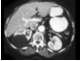

82.患者,男,55岁,右侧腰、腹部偶尔不适1年余,CT影像如图所示,其最可能的诊断为()